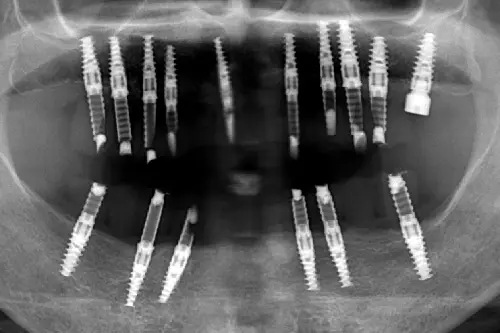

インプラントを埋め込む本数も、術後の痛みに影響します。1本だけの埋入であれば、手術時間は短く、体への侵襲も最小限で済みますが、複数本を同時に埋入する場合や、「オールオン4」のように顎全体の治療を行う場合は、当然ながら治療時間が長くなる分、身体への負担が増します。

手術範囲が広くなれば、それだけ術後の炎症反応も広範囲に及ぶため、痛みや腫れのピークが強く出たり、長引いたりする可能性があります。多数歯の治療を行う場合は、仕事や予定を入れてもいいか、担当歯科医師と相談の上スケジュールを組みましょう。